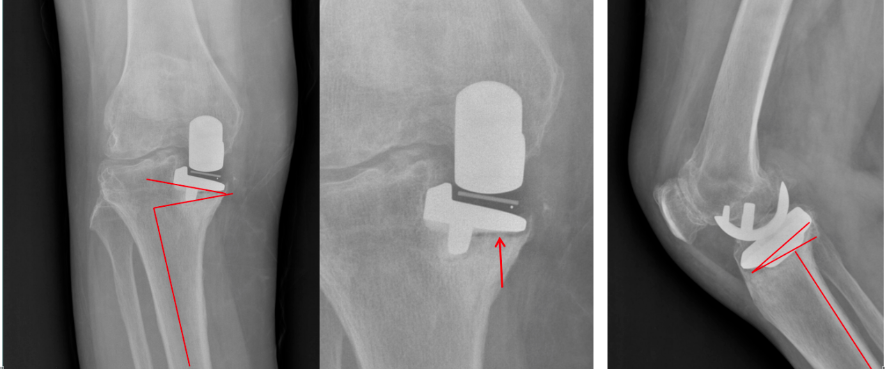

髋臼杯假体的前倾角相对于股骨假体的前倾角来说比较容易调整,为了使假体的联合前倾角在安全范围内,有学者提出“股骨侧优先”的理念。术中先进行股骨扩髓,确定股骨柄的前倾角,然后调整髋臼杯的前倾角,髋臼杯的前倾角=计划的联合前倾角(25°-50°,平均37°)-股骨柄的前倾角。在Y asuharu有关联合前倾角的文章中,采用股骨侧优先的的理念,未使用联合前倾角技术的脱位率是使用联合前倾角技术的5.8倍。

髓腔锉的前倾角:在扩髓至最后的髓腔锉肩部,保留该髓腔锉,屈膝使小腿垂直于地面,用量角器测量髓腔锉的前倾角。

髋臼杯前倾角(C)定义为在矢状面上测量的前倾角

王先泉等人采用股骨侧优先的概念,并采用Y asuharu 的方法测量股骨假体前倾角,术后患者全部符合Dorr等提出的25°-50°的安全区标准,术后无患者发生脱位。对与术中联合前倾角的测试,一般采用Coplanar试验测量联合前倾角:髋关节复位后,伸髋0°、屈膝90°、大腿与地面平行,从头侧观察,内旋大腿使股骨假体颈与髋臼杯假体平面垂直(股骨头假体边缘与内衬边缘平行,股骨头假体前部和后部外露面积相等),此时小腿与水平面所成的角度(髋关节内旋的角度)即为联合前倾角。